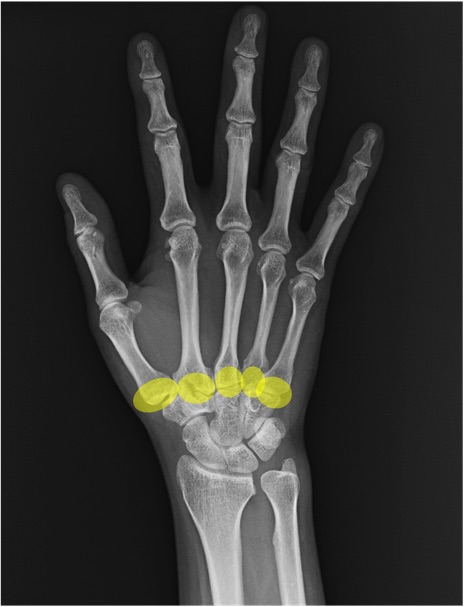

CM関節(carpometacarpal joint)の手関節レントゲン画像における正常解剖

症例

舟状骨(scaphoid)

月状骨(lunate)

三角骨(triquetrum)

中手骨(metacarpal bone)

基節骨(proximal phalanx)

中節骨(middle phalanx)

末節骨(distal phalanx)

橈骨(radius)

尺骨(ulna)

尺骨茎状突起(ulnar styloid process)

IP関節(interphalangeal joint)

MP関節(metacarpophalangeal joint)

PIP関節(proximal interphalangeal joint)

DIP関節(distal interphalangeal joint)